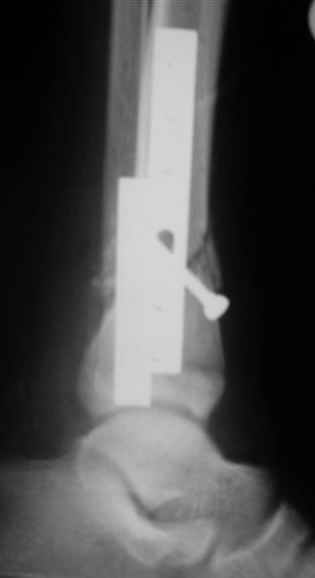

АВФ -отдельная история в нашем краю, поэтому последний вариант -открытая репозиция, что я и сделал: Без мобилизации отломков б.б. репозиция м.б. не получалась. Первым делом фиксировал перелом м.б. кости пластиной на 4 4,5 мм винтах,

при ревизии зоны перелома б.б. кости сохранялось смещение дистального отломка кпереди, пришлось принять меры и решить эту проблему.

*укрепить* достигнутое положение узкой пластиной динамической компрессии.

Послеоперационные снимки сегодня посмотрел - все выглядит вполне анатомично, кроме длины

винтов на м.б. кость - слегка переборщил:-(( Не было камеры с собой , но как только

Помятуя наш недавний разговор о фиксации м.б. кост, высылаю послеоперационные картинки..

Напомню- разбирали случай 17 летнего молодого человека перелом дист тиб.фиб. хирургия после 3 недель с момента травмы( безуспешные попытки закрытой репозиции) Раны заживают первичным натяжением, занимается физиотерапией, пока никаких проблем не наблюдается